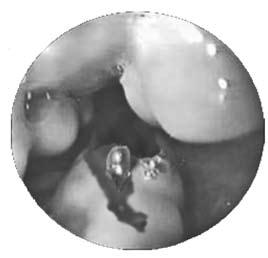

Рис. 83. Эндоскопическая картина при варикозном расширении вен пищевода с признаками кровотечения

Рис. 85. Эндоскопическое лигирование варикозных вен пищевода

Для каждого вида кровотечения применяют свой метод гемостаза. Важно выбрать адекватный способ, поскольку второй попытки остановки кровотечения может и не представиться. Для определения источника кровотечения используют срочную фиброэзофаго‑гастродуоденоскопию (ФЭГДС), во время которой подтверждают диагноз варикозного расширения вен пищевода, определяют зону нарушения целостности вены и интенсивность кровотечения. При умеренном кровотечении из варикозных вен пищевода, синдроме Мэллори‑Вейса или язвы двенадцатиперстной кишки сразу может быть предпринята попытка его эндоскопической остановки. Наиболее эффективным методом остановки кровотечения из варикозных вен пищевода является их эндоскопическое лигирование. При этом эффективность метода достигает 90 %, а количество рецидивов составляет примерно 10 % (рис. 85).